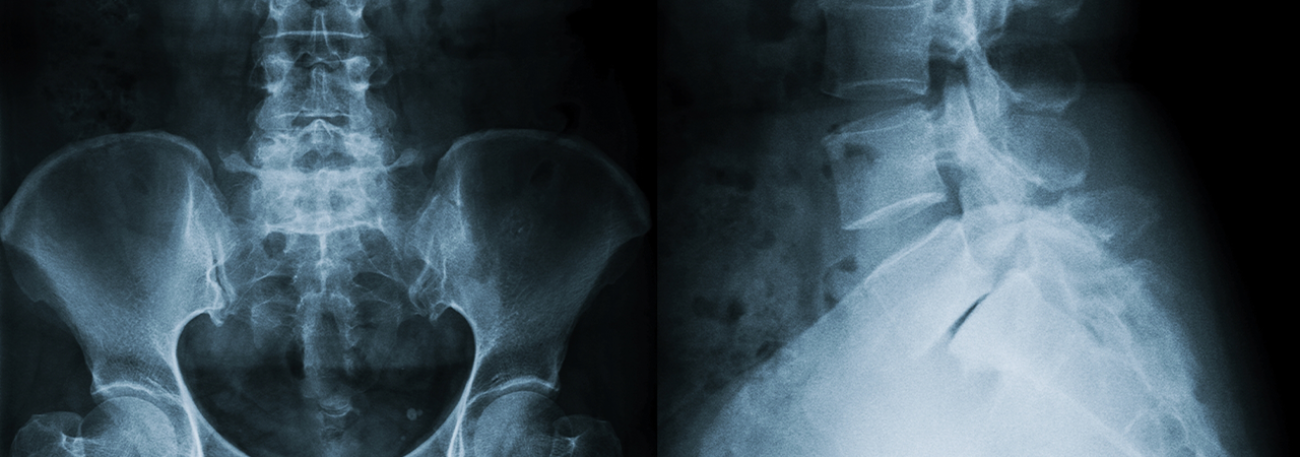

Digitales Röntgen

Sämtliche konventionelle Röntgenaufnahmen führen wir in digitaler Technik durch, inklusive Thorax-, Abdomen und Skelettaufnahmen. Die Röntgendokumentation erfolgt ebenfalls digital.

Das Angebot umfasst sämtliche konventionellen digitalen Röntgenaufnahmen für Thorax-, Abdomen- und Skelettaufnahmen, Ultraschalluntersuchungen für Weichteile, Ganzkörper-Computertomographie und MRI-Untersuchungen.